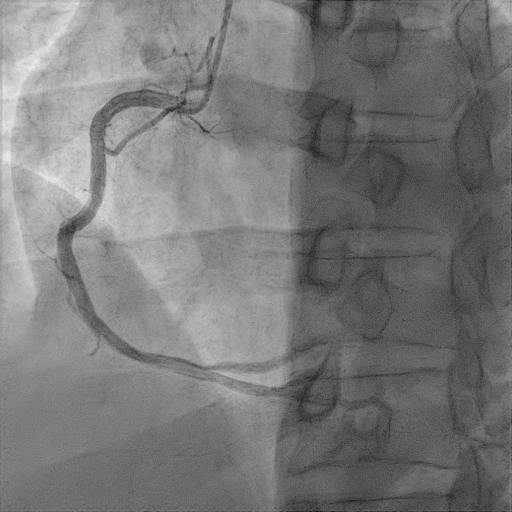

간단히 환자의 관상동맥 조영술 결과를 살펴보자

관상동맥조영술(coronary angiography) 결과 환자는 proximal LAD(left anterior descending)의 total occlusion으로 TIMI flow** 0점이었다.

관상동맥 협착으로 혈류량을 나타내는 지표인 TIMI flow로 0점은 혈관이 완전히 막혀서 혈류가 없는 상태, 3점은 정상 혈관으로 혈류가 완전한 상태를 타나 내며 0~3점 총 4단계로 표시한다.